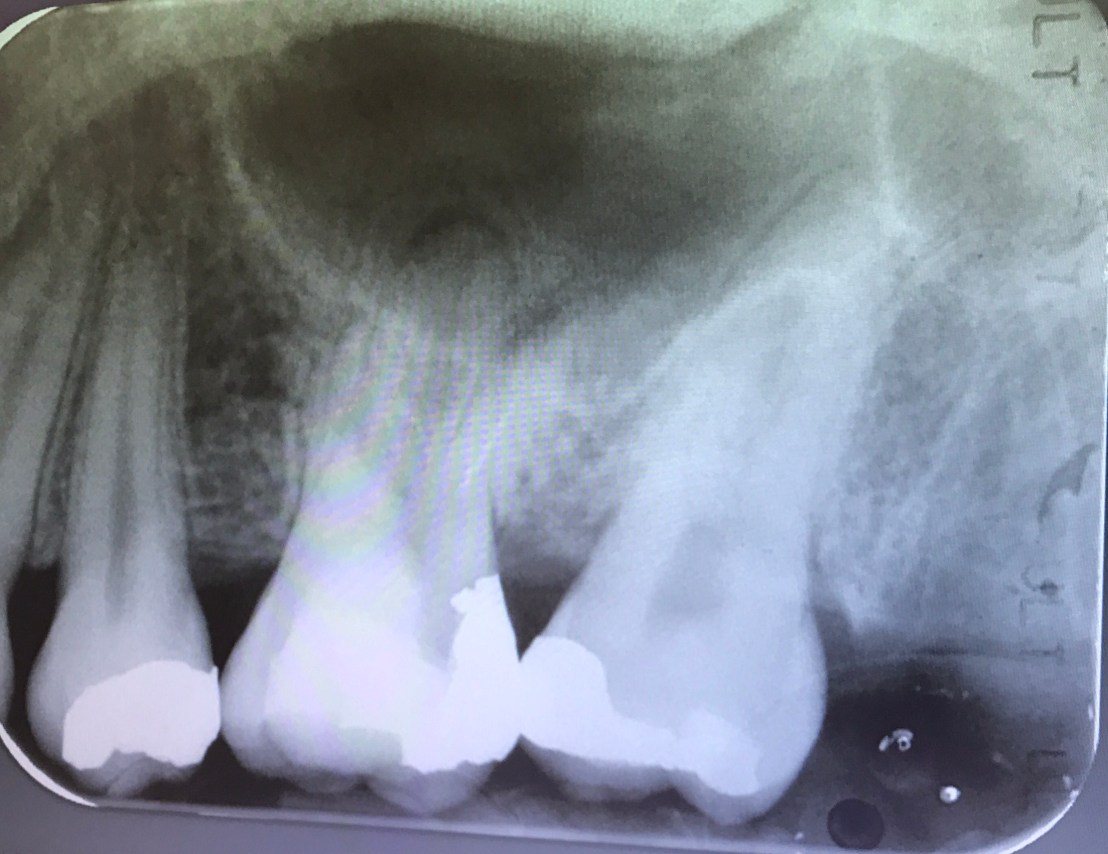

ฟัน #36, 46 คือฟันที่ท่านอาจารย์เตรียมไว้ให้สำหรับการฝึกการรื้อเครื่องมือและการซ่อมรอย perforate ในช่วงบ่าย

case แสดง Root canal retreatment ฟันซี่นี้มี Post หักที่ Distal root

อันนี้คือ case จริงครับ ส่วนที่ Outline ไว้ตรงกลางคือ รอย Perforate

อีก case

จุดสีเหลือง คือ canal ที่ถูกต้อง

วงกลมสีแดง แสดงส่วนที่ถูก repair ด้วย MTA